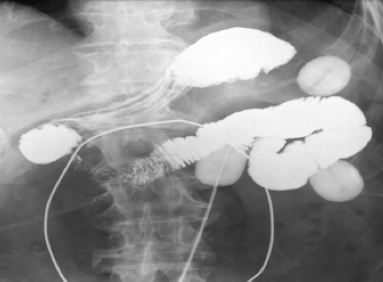

При наружных свищах проводится фистулография (введение контрастного вещества в свищ). Следует уделить внимание обязательному попаданию контраста в отводящую петлю с целью выяснения скорости пассажа контрастного вещества по кишке, обнаружения его задержки и определения уровня этой задержки. Данная информация имеет значение для хирургического вмешательства, при котором необходимо ликвидировать сам свищ, а также перегибы и деформации отводящей петли. Это позволит избежать гипертензии в области швов анастомоза в послеоперационном периоде.

При внутренних свищах осуществляется введение контрастного вещества через рот.

При наружных свищах контрастирование через рот также необходимо для выяснения состояния приводящей петли свища - ДПК и/или желудка.

Для оценки состояния внутренних органов, взаимоотношения их со свищевым ходом может потребоваться УЗИ органов брюшной полости, мультисрезовая спиральная компьютерная томография органов брюшной полости, обзорная рентгенография органов брюшной полости. Также широкое применение нашли рентгенконтрастные методики: рентгенография пассажа бария по тонкому кишечнику, ирригоскопия, фистулография (введение контраста в свищевой ход).

- Фистулография. Является наиболее распространенным визуализационным методом диагностики наружных свищей. Контраст вводят в отверстие, по данным снимков определяют пораженный орган, точную локализацию фистулы, направление хода, наличие затеков.

- Рентгенография с контрастированием. При внутренних поражениях проводят ирригографию, рентгенографию желудка или пищевода с барием. Контраст выходит через стенку органа на кожу, в соседние органы или полости, что позволяет уточнить особенности свища.